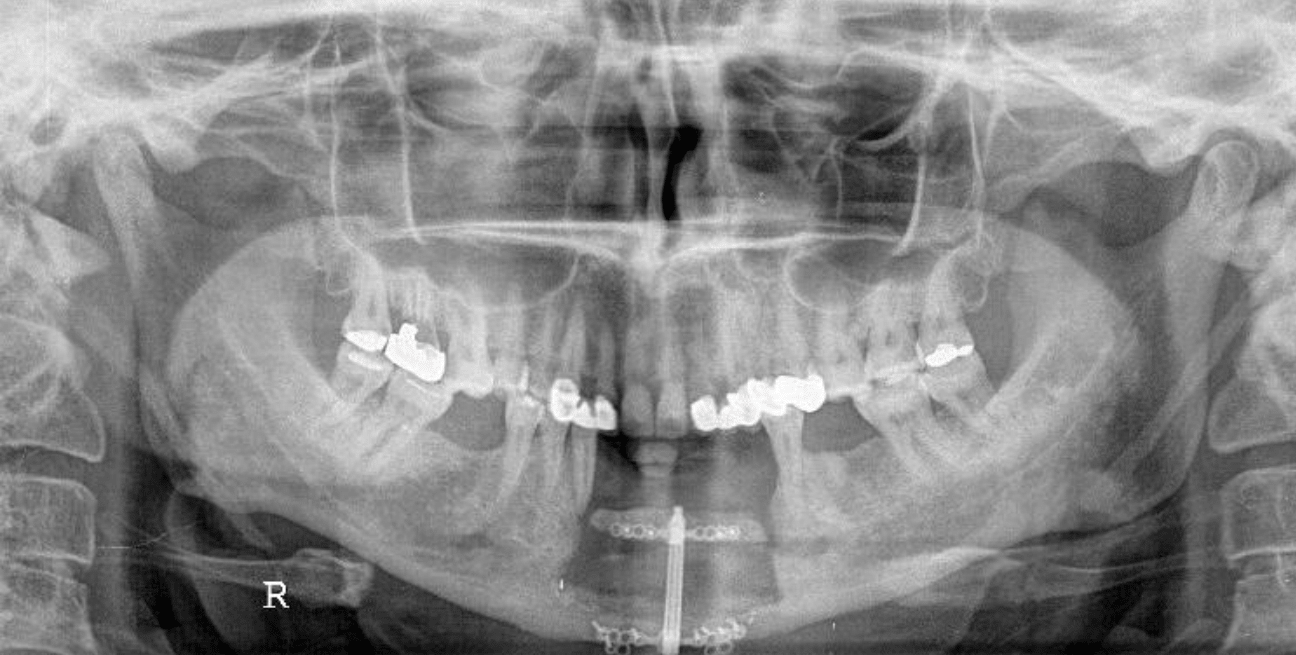

Preoperative radiographic examination including panoramic X-ray and C.T for evaluation of mandibular bone invasion by the lesion and evaluation of the neck lymph nodes (Figure 2A, B, C). Both the mandibular bone and neck lymph nodes were free. Whole body scan with Technetium-99m radiopharmaceuticals imaging was negative (Figure 2D). Clinical stage according to TNM system was T1N0M0.

Figure 2a CT axial view for evaluation of bone invasion by GSCC.

Figure 2b CT axial view for evaluation of bone invasion by GSCC.

Figure 2c CT coronal view for evaluation of bone invasion by GSCC.

Figure 2d Negative whole body scan with Technetium 99.